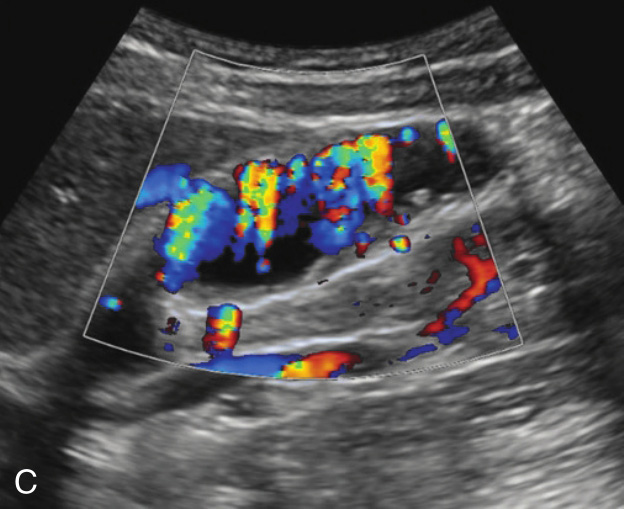

(3)弥漫型胆囊腺肌症:

又称广泛型,胆囊壁呈广泛性增厚(图2-4-3),部分病例胆囊壁上可见多发点状强回声。

图2-4-3 弥漫型胆囊腺肌症常规超声图像

A.胆囊壁呈弥漫性增厚;B.高频超声显示增厚的胆囊壁上可见多发点状强回声;C.CDFI显示“快闪伪像”